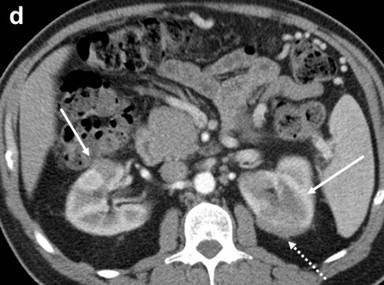

The patient was referred to our institution for consultation where he underwent repeat multiplanar MDCT with the use of 100 mL intravenous (iopromide; Ultravist® 300, Bayer, NJ, USA) contrast material delivered at 3 mL/s and imaged with a 70 s delay. Nine hundred mL oral (water) contrast was also utilized. Images were obtained at 120 kVp and 200 mAs and reconstructed at 5 mm. The pancreas was universally enlarged with a distinct rim of hypoattenuation (Figure 1). The wall of the gastric body and fundus, predominantly posteriorly, was diffusely thickened, measuring up to 1.4 cm, and had a nodular appearance (Figure 1). The gastric wall thickening spared the antrum. No hyperenhancement of the gastric wall was noted. There were additionally noted several hypodense lesions in both kidneys that were surrounded by hypovascular soft tissue (Figure 1) as well as focal jejunal wall thickening without hyperenhancement (Figure 1).

Figure 1. a. Axial MDCT image of the abdomen with intravenous and oral contrast demonstrates a thickened, “sausage-like” pancreas with a hypodense rim of tissue (arrow). b. Axial MDCT image of the abdomen with intravenous and oral contrast demonstrates a thickened and nodular appearance of the stomach wall at the level of the gastric body measuring up to 1.4 cm (arrow). c. Sagittally reformatted MDCT image of the abdomen shows the thickened and nodular gastric body wall, most pronounced posteriorly (arrow). d. Axial MDCT image demonstrates bilateral renal lesions (arrows) with a soft tissue attenuation within and immediately adjacent to the left kidney (dotted arrow). e. Axial MDCT image demonstrates focal jejunal wall thickening. |

In our case, additional clues both suggested and supported the diagnosis. The salivary and lacrimal glands are often involved in IgG4-associated disease. Review of the patient’s previously excised submandibular salivary gland confirmed the presence of IgG4-positive plasma cells within a lymphoplasmacytic infiltrate containing dense bands of fibrosis. Renal lesions that have previously been described in conjunction with this entity were also observed in this patient. Though the sigmoid colon was noted to have IgG4-positive plasma cells on biopsy, it did not demonstrate any radiologic abnormality. The small bowel, however, had focal areas of wall thickening likely associated with this entity, although no biopsies were taken in this area.